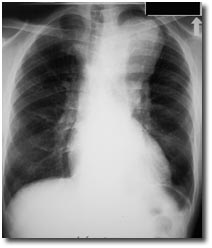

bd_res_emim_cc_cxr.jpg